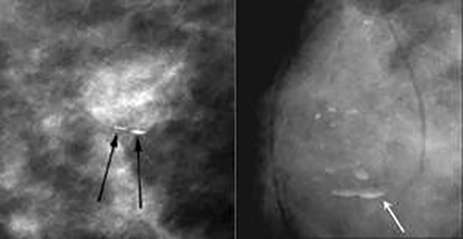

Rim Calcifications

Rim Calcifications: Include the previously described “eggshell” and “radiolucent centered” calcifications. These correspond to calcifications along round lesions such as oil cysts or simple cysts. These are usually associated with history of trauma or surgery.

Milk of calcium calcifications

Milk of Calcium Calcifications: Craniocaudal View

Milk of calcium calcifications: True lateral views